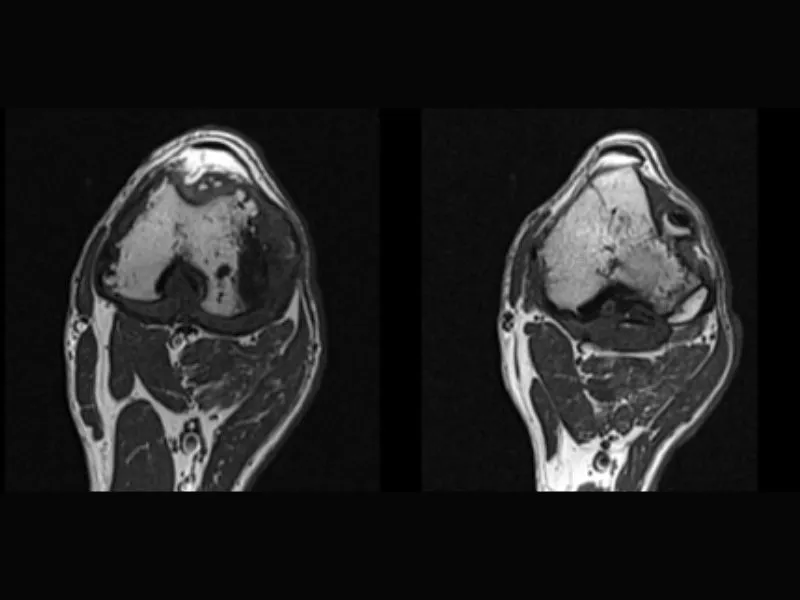

Clinical images

Small animals